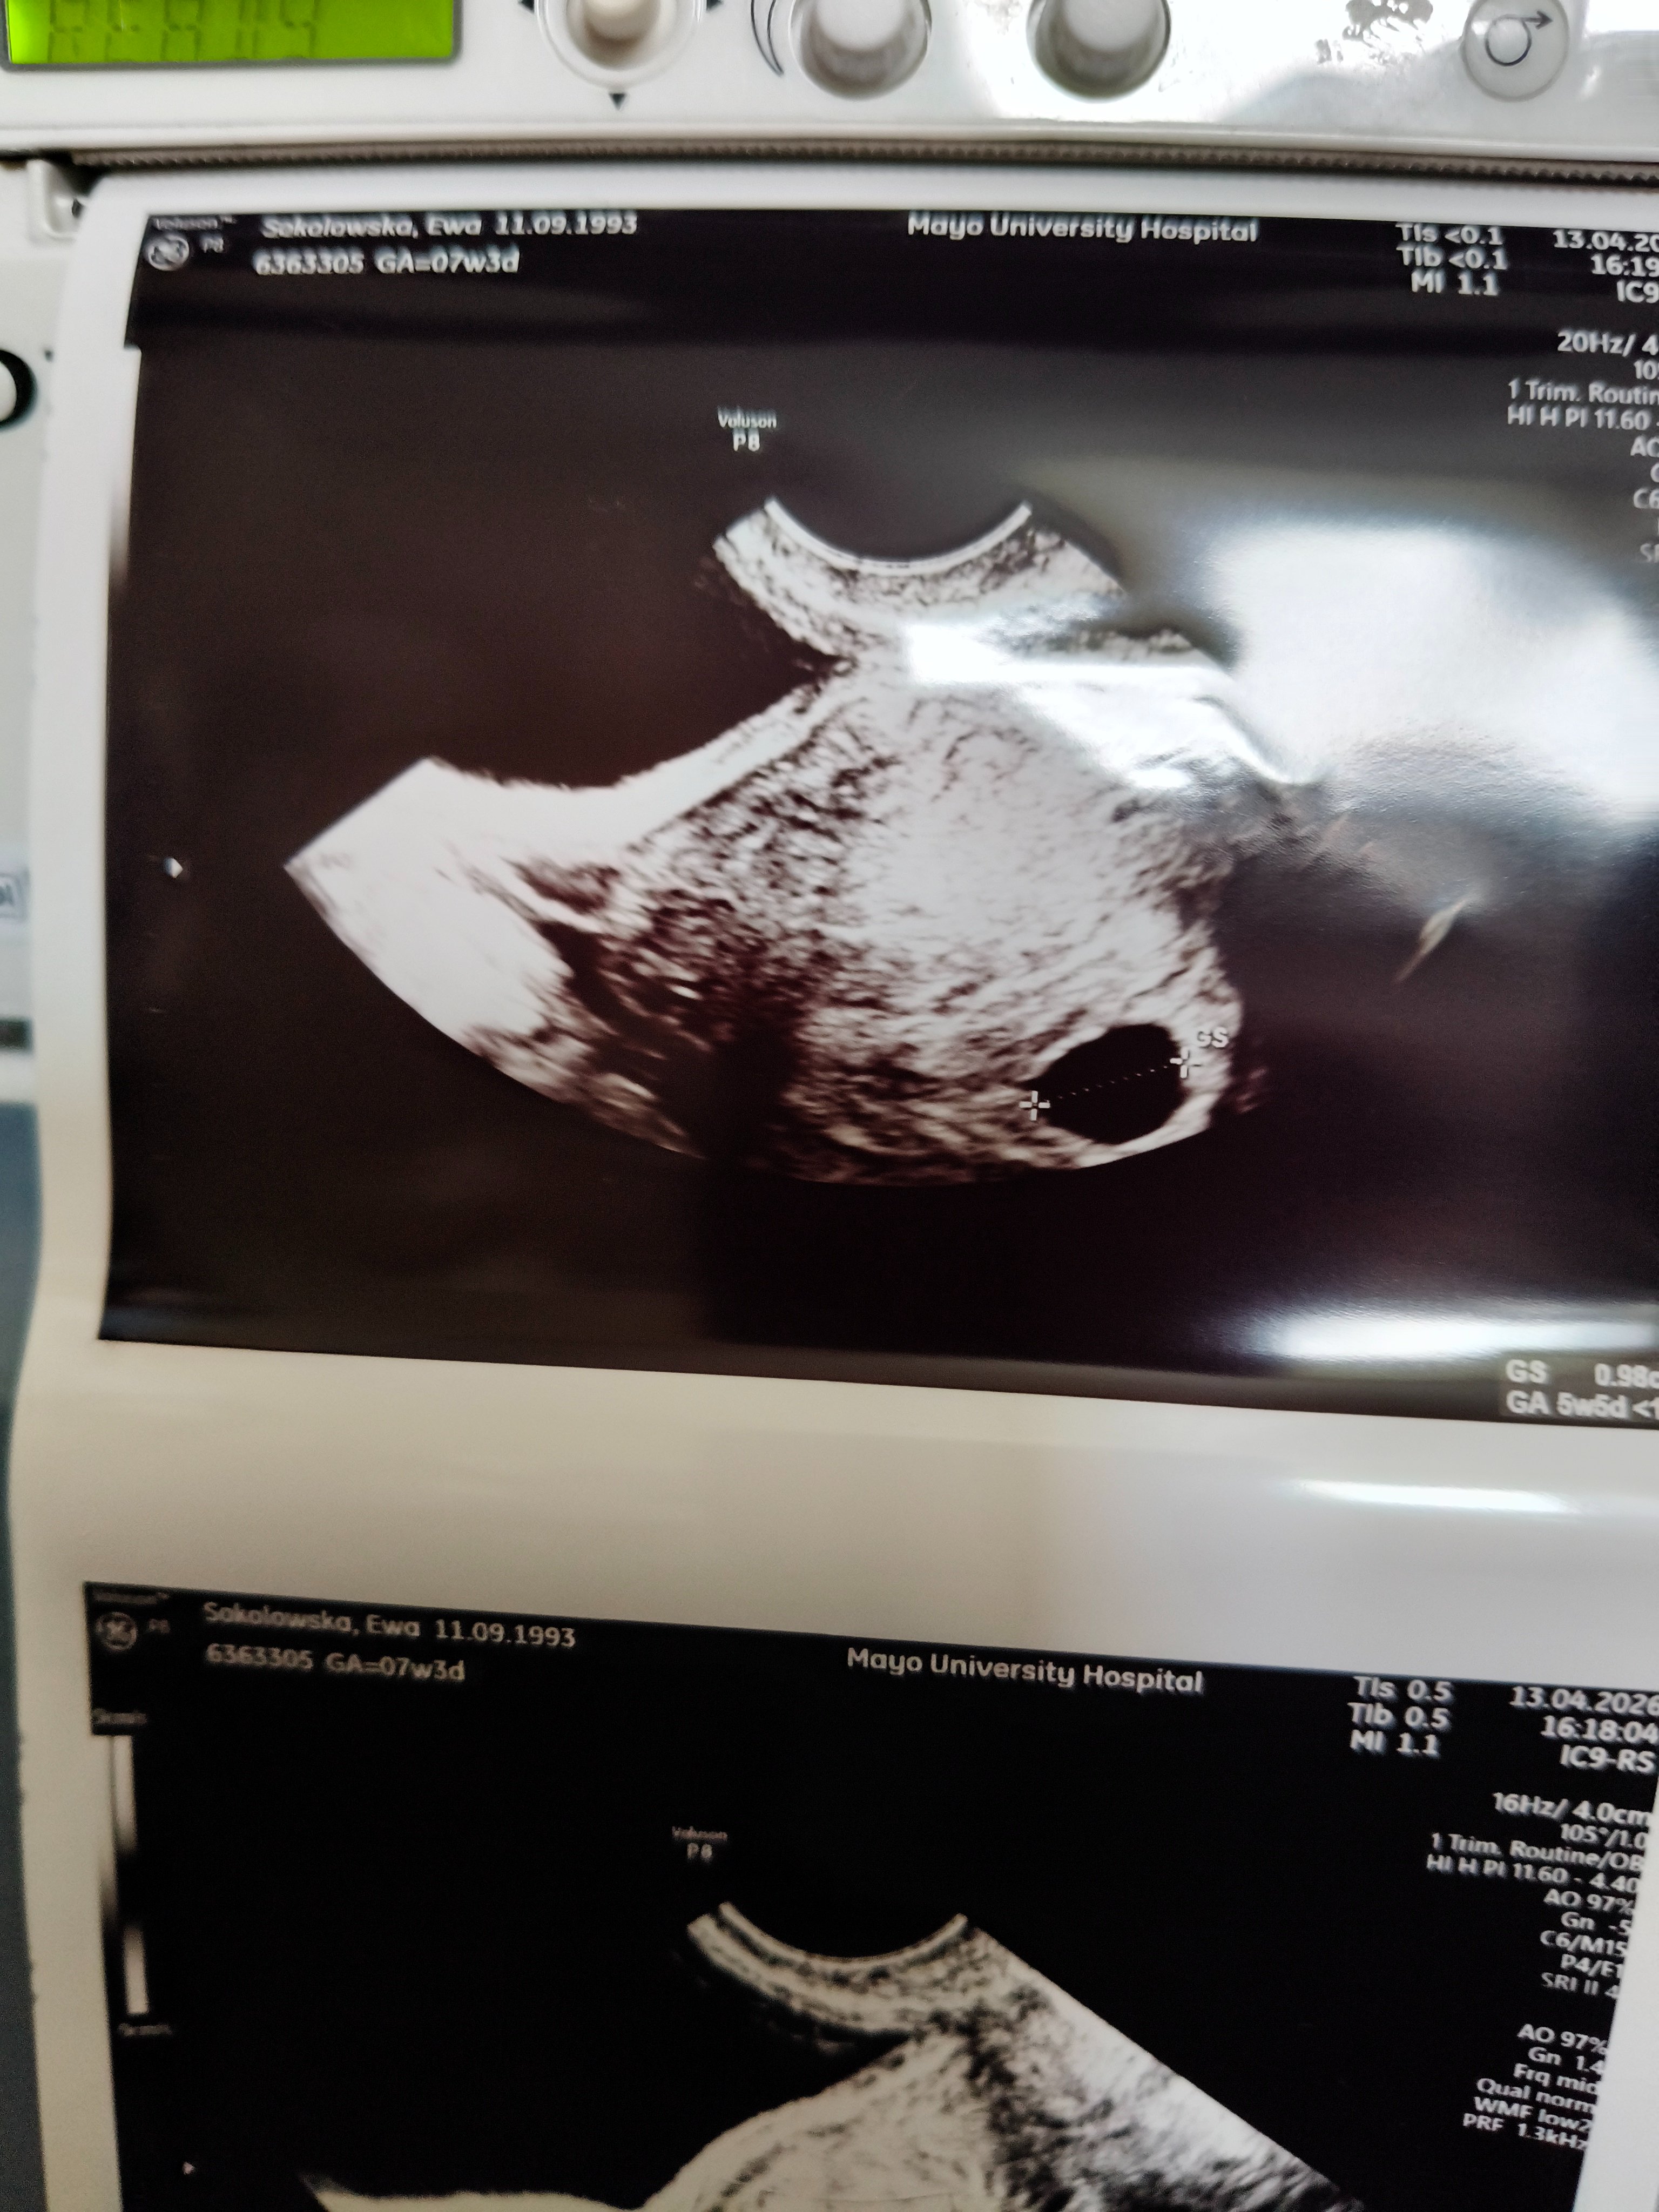

Hejka nie wiem gdzie tu napisać ale potrzebuje małej porady w pon wylądowałam w szpitalu z krwawieniem,nic tam się nie zmienia jest dalej pusty worek tym razem mam zdjęcie.mam jutro podjąć decyzję na to jak mają oczyścić czy któraś z was to przechodziła lepsze łyżeczkowanie tabletki czy czekać aż samo się rozkręcił...

Mnie trzymają sama nie wiem czemu.dzis miałam kolejny scan i muszę czkeac do następnego piątku,a to bardzo meczu glowe